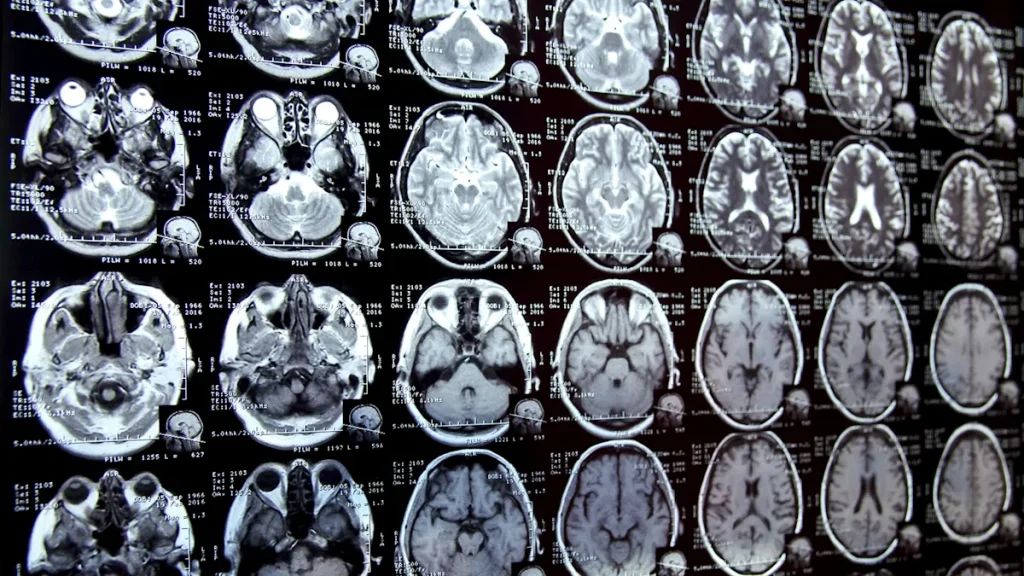

In a groundbreaking study led by researchers at the University of New Mexico, scientists found that brain samples in 2024 contained nearly 50% more microplastics than eight years earlier. The average brain holds about seven grams of plastic – the equivalent weight of a disposable spoon.

Even more worryingly, researchers observed higher levels of microplastics in the brains of people with dementia, although, as the Times noted, scientists at the lab “suggested that this may be because the blood-brain barrier in these brains is more porous and less able to clear out toxins.” Similar plastic particles have been found in human placentas, blood, and even babies’ first stools.

Once inside the body, some microplastic particles are so small that they can pass through critical barriers and become lodged in organs such as the brain. While scientists haven’t yet determined how much plastic is too much, early findings suggest plastic is definitely dangerous.

Current research shows links between microplastics and serious health problems, including cognitive decline, reproductive problems, immune system disruption, memory loss, hormonal disruptions, and even childhood developmental issues. Since most plastic waste is decades old, this isn’t just a problem for the future, it’s already here.